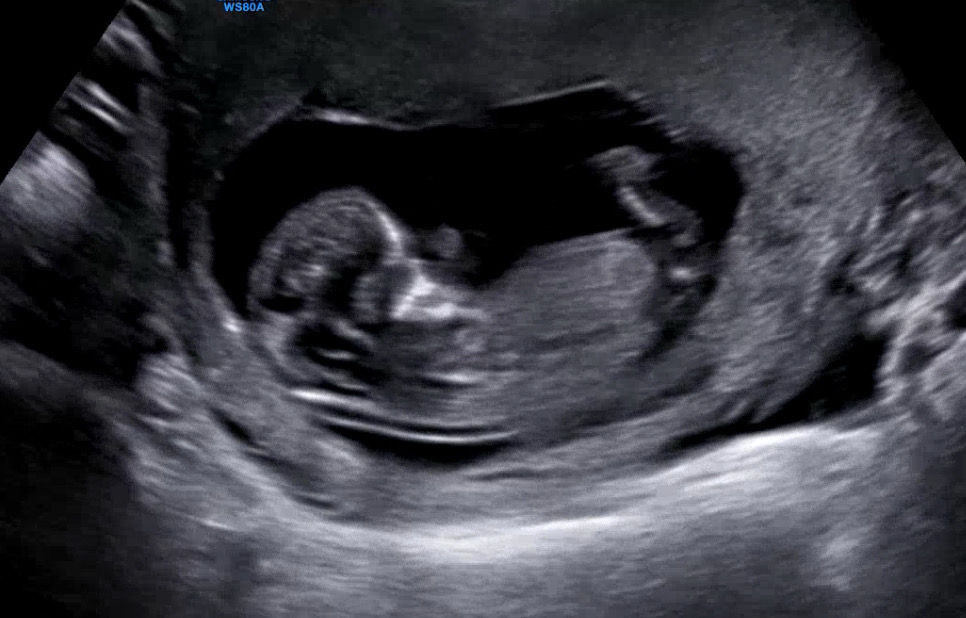

오늘 12주차 1차 기형아검사하고 왔어요! 저번에 아기집이 작아서 아기가 낑겨있던 것 같아서 맘 아팠는데 오늘은 확실히 여유가 생겼어요!ㅎㅎ 오늘 찍은 사진으로 각도법 판단 가능할까요?